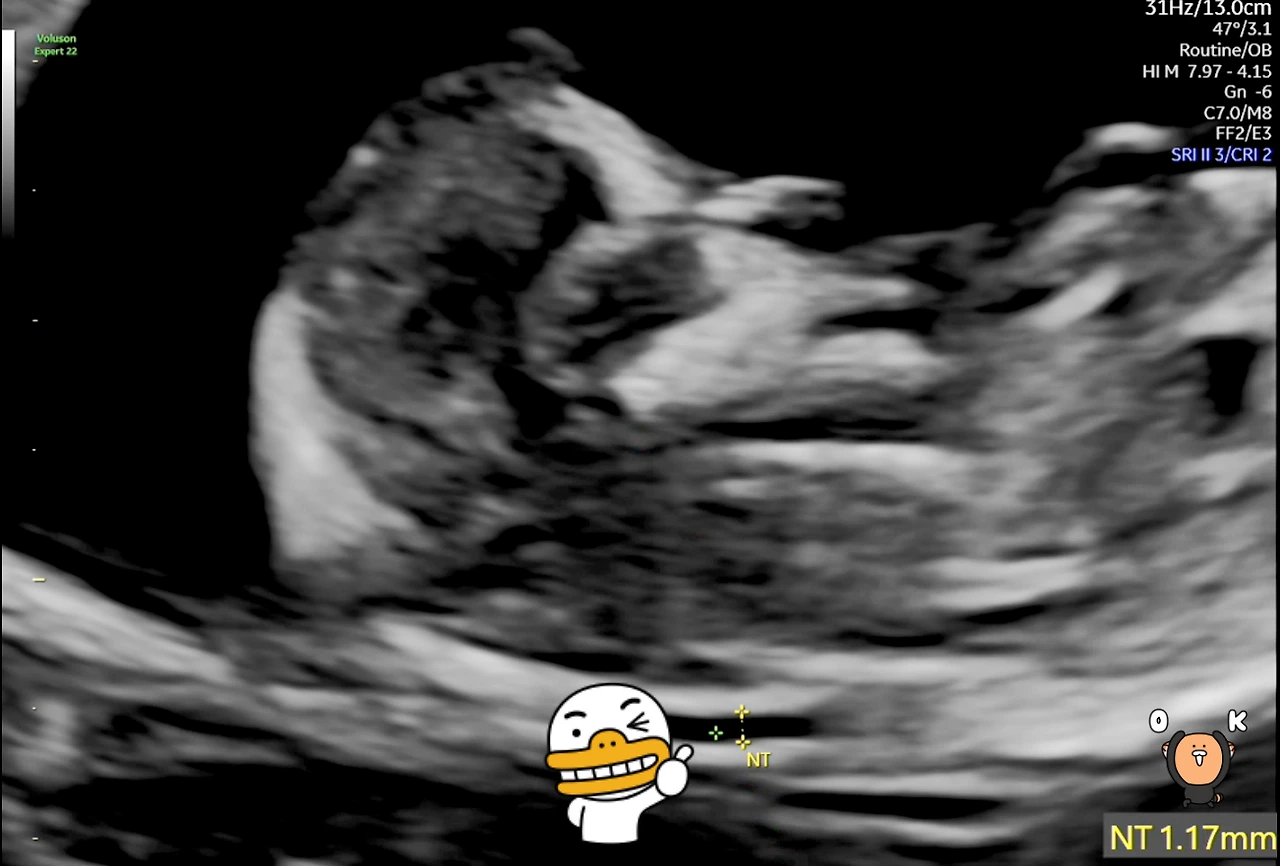

그나저나 가장 궁금한 것이 태아 목덜미 투명대(NT: Fetal Nasal Translucency)인데, 다른 것만 보다 보니 주객이 전도되었네요. 목둘레 투명대의 두께는 평균 1.0~1.5mm 사이로 나오는데 3.0mm가 넘는 경우 '다운증후군(Down Syndrome) 등의 기형의 우려가 있다고 합니다.

'팡팡이'의 NT는 1.17mm로 정상범위 내라서 다행입니다.

12주차 태아 목둘레.PNG [태아 목덜미 투명대(NT)]